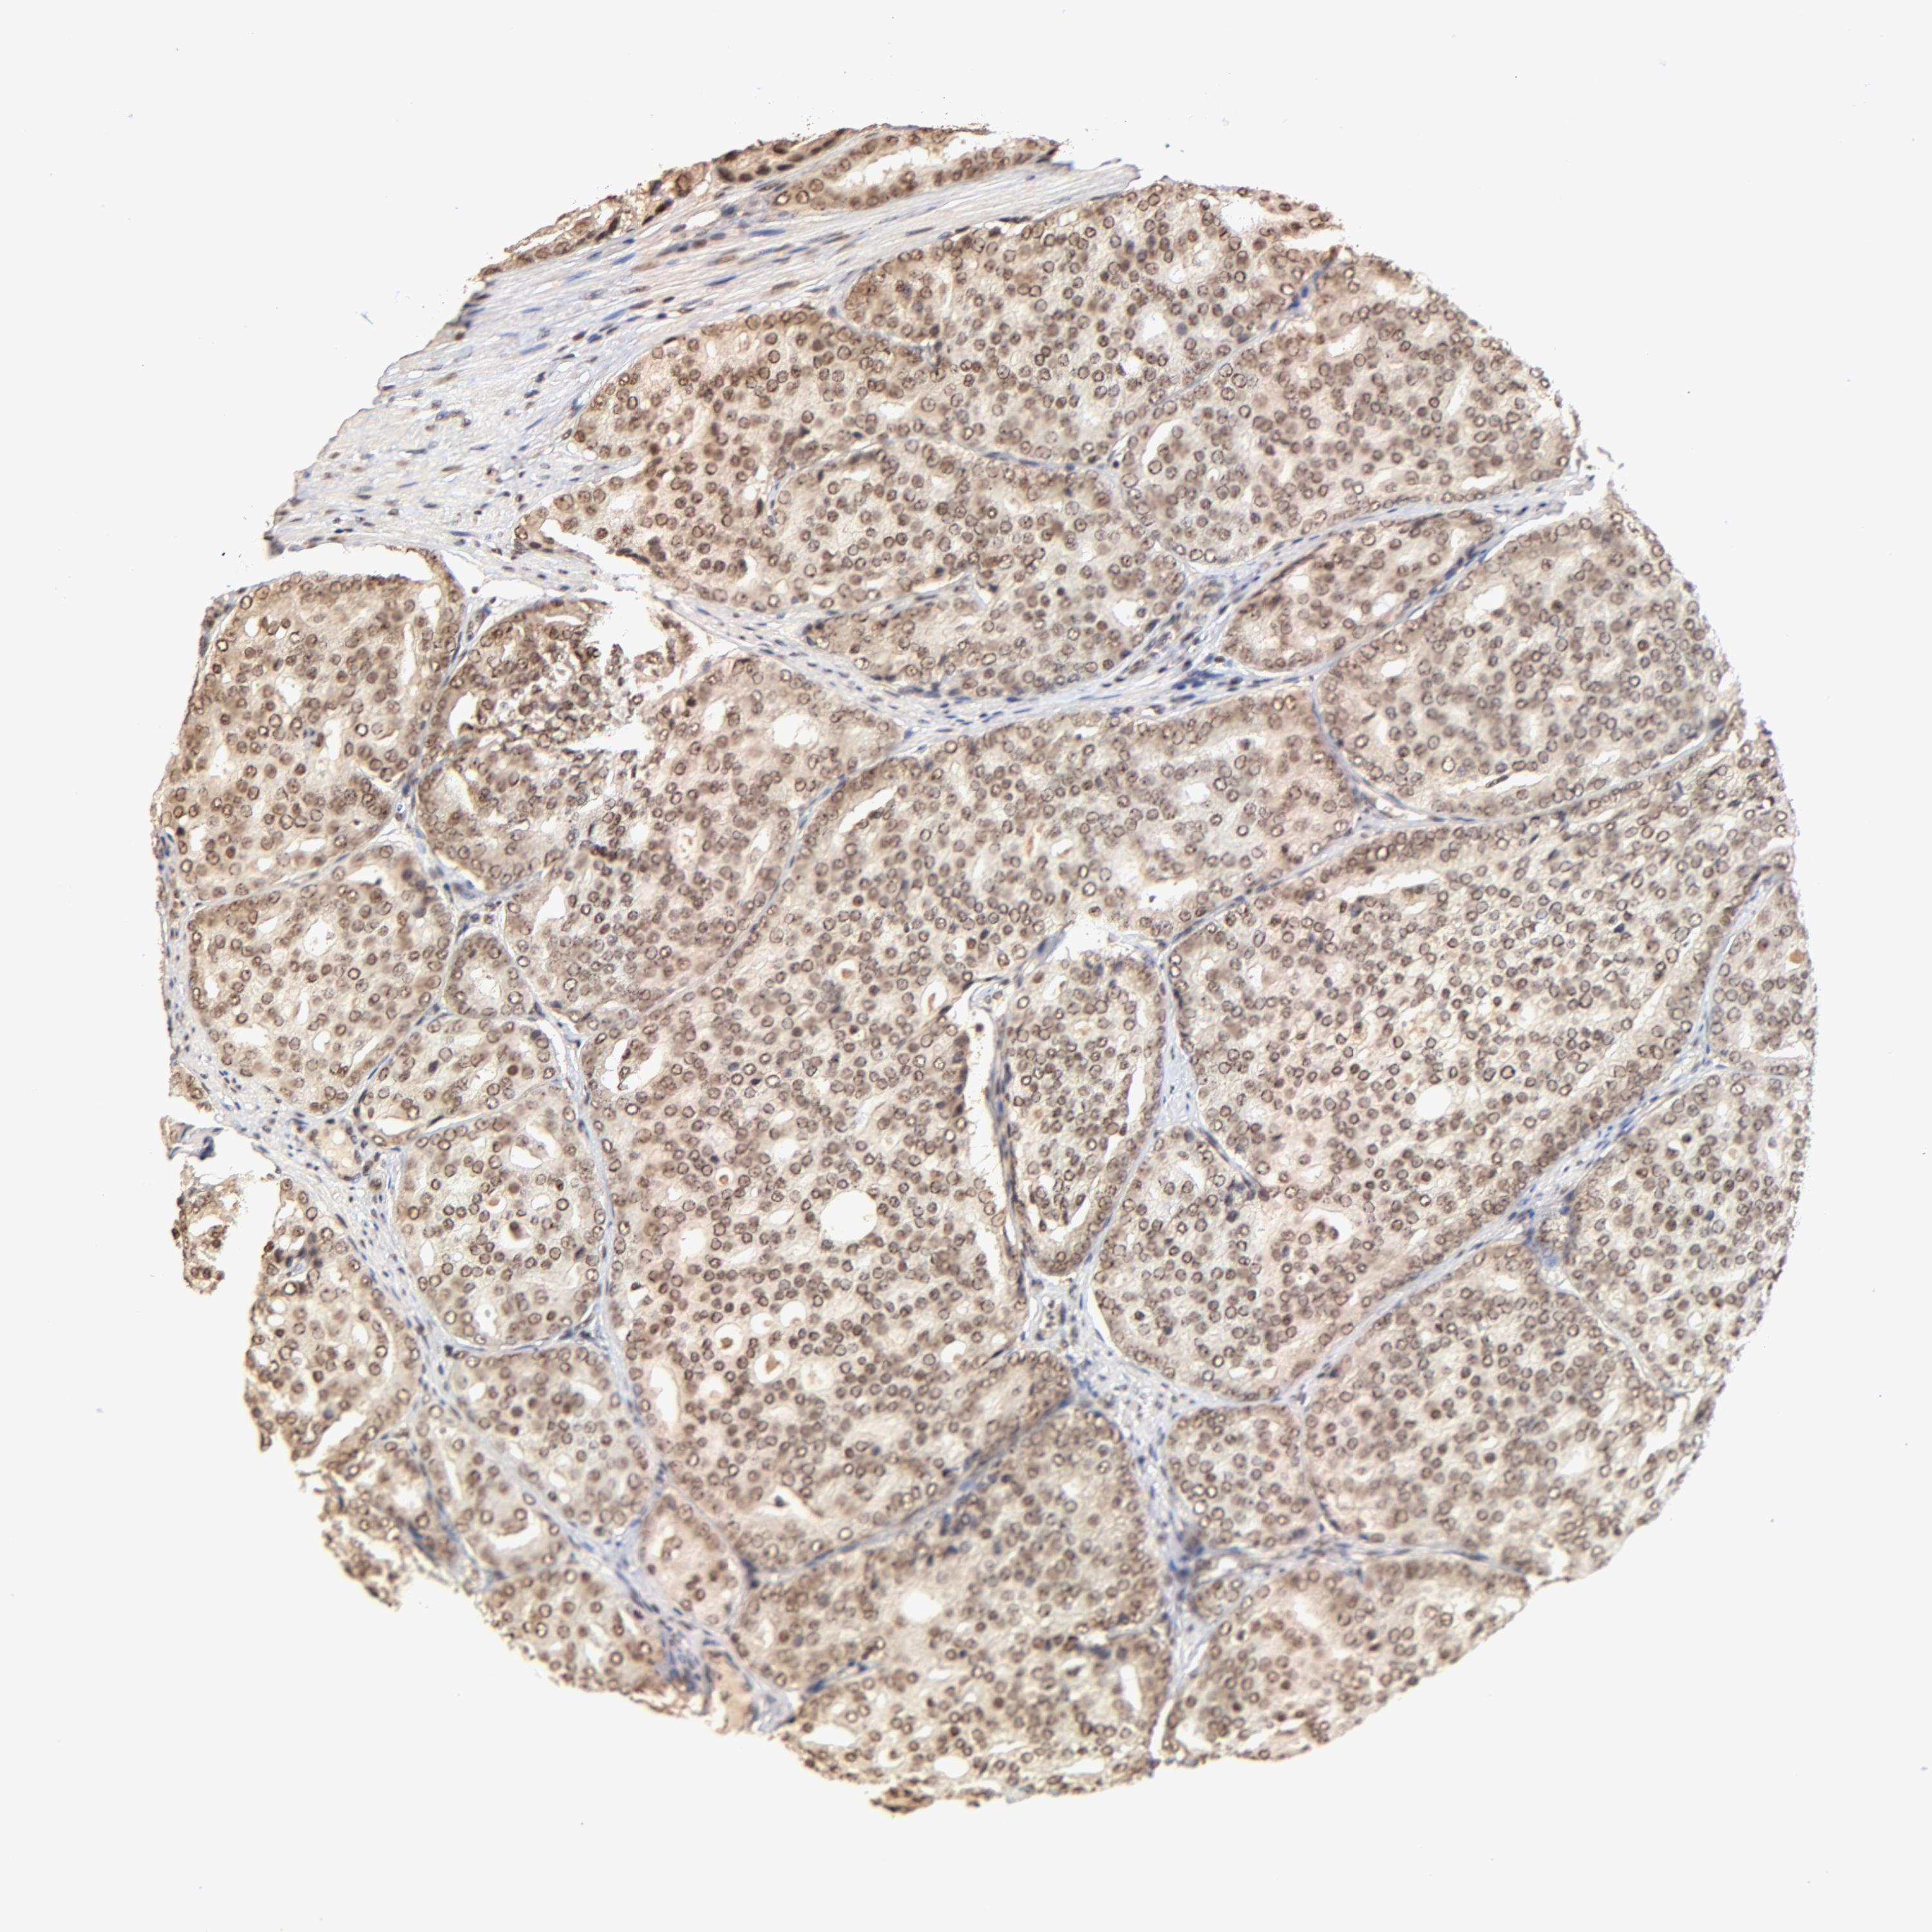

PROSTATE CANCER - Protein expressioni

A mouse-over function shows sample information and annotation data. Click on an image to view it in a full screen mode. Samples can be filtered based on level of antibody staining by selecting one or several of the following categories: high, medium, low and not detected. The assay and annotation is described here.

Antibody stainingi

Antibody staining in the annotated cell types in the current human tissue is reported as not detected, low, medium, or high, based on conventional immunohistochemistry profiling in selected tissues. This score is based on the combination of the staining intensity and fraction of stained cells.

Each image is clickable and will lead to virtual microscopy that enables deeper exploration of all samples and also displays staining intensity scores, fraction scores and subcellular localization as well as patient and tissue information for each sample.

Antibody HPA003184

Antibody HPA003185

Staining

High

Medium

Low

Not detected

Intensity

Strong

Moderate

Weak

Negative

Quantity

>75%

75%-25%

<25%

None

Location

Nuclear

Cytoplasmic/membranous

Cytoplasmic/membranous,nuclear

Adenocarcinoma, Low grade

Adenocarcinoma, Medium grade

Adenocarcinoma, High grade